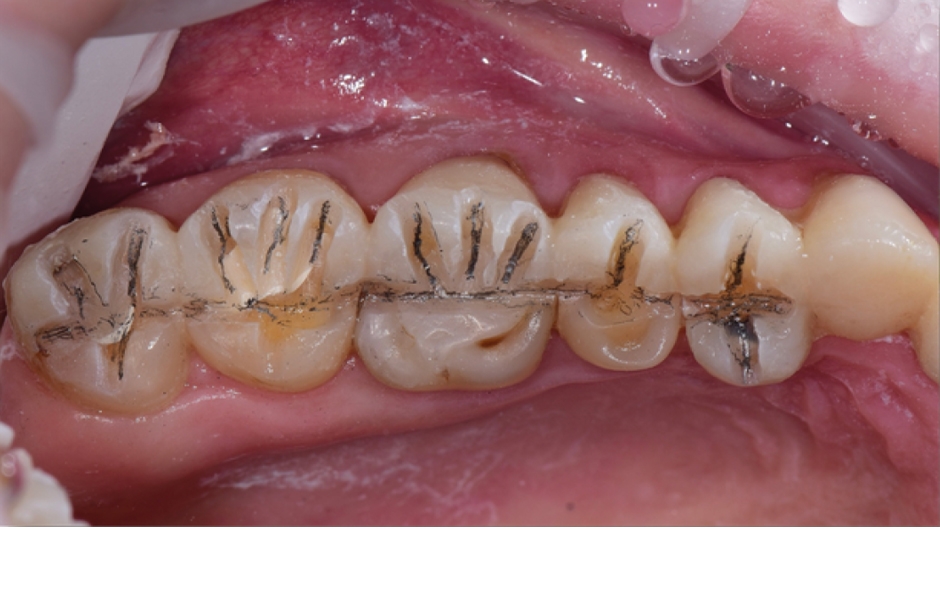

Případ č. 2: obr. 6

Případ č. 2: obr. 7

Případ č. 2: obr. 8

Případ č. 2: obr. 9

Případ č. 2: obr. 10

Případ č. 2: obr. 11

Případ č. 2: obr. 12

Případ 2: Preparace horních distálních zubů s použitím mock-upu – první fáze kompletní rekonstrukce okluze. Po prvotní preparaci jsem na rekonstrukci zubů použil nový materiál Charisma Bulk Flow ONE.

Materiál Charisma Bulk Flow ONE je možno použít ve vrstvě o tloušťce až 4 mm bez dodatečné krycí vrstvy. Díky chameleon efektu výplň barevně splyne s okolními tvrdými tkáněmi. Jeho odolnost vůči abrazi je podobná kompozitům ve formě pasty určeným pro distální zuby. Je rentgenkontrastní a má fenomenální povrchové pnutí. Materiál přesně zateče k okrajům preparace, aniž by je přesáhl.

Poté, co jsem zhotovil výplně zubů, přistoupil jsem k závěrečné preparaci pro overlaye. Správně naplánovaná preparace mi umožnila docílit optimálního prostoru pro umístění provizorní náhrady v podobně 5 spojených členů, kterou jsem zhotovil nepřímo a nacementoval provizorním cementem (v tomto případě jsem použil karboxylový cement).